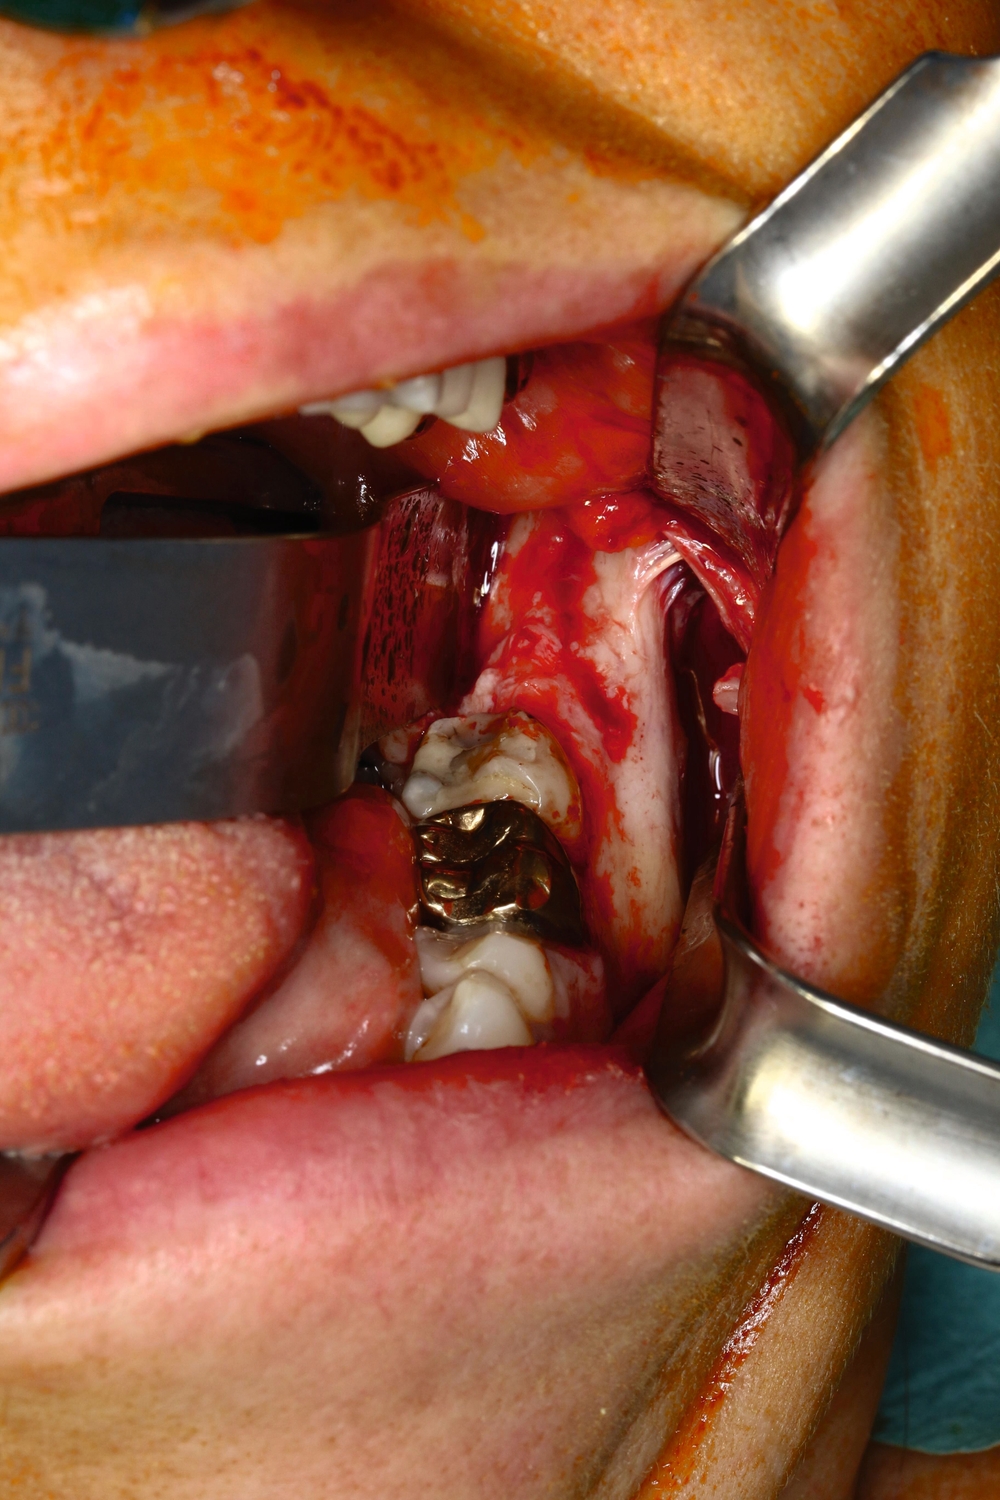

Der operative Zugang erfolgte über eine marginale Schnittführung von Zahn 36 bis 37 mit mesialer vestibulärer Entlastung sowie distaler Fortführung auf der Linea obliqua des Ramus mandibulae (Abbildung 3a). Nach Anpassen einer 8-Loch-Osteosyntheseplatte (Synthes MatrixMANDIBLE) wurde die vestibuläre Kortikalis piezochirurgisch osteotomiert. Nach Entfernung des Knochendeckels konnte die Raumforderung dargestellt und die subtotale Invagination des Nervus alveolaris inferior bestätigt werden (Abbildung 3b). Die Raumforderung konnte vollständig unter Nervschonung entfernt werden (Abbildung 3c). Die vestibuläre Kompaktaschale wurde an der zur Stabilisierung eingebrachten Osteosyntheseplatte refixiert.